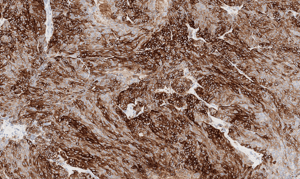

Our screen includes 38 models across head and neck, neuroendocrine, and other clinically relevant tumor types. Each model is annotated with SSTR2 expression data and optimized for radiopharmaceutical evaluation.

Histology